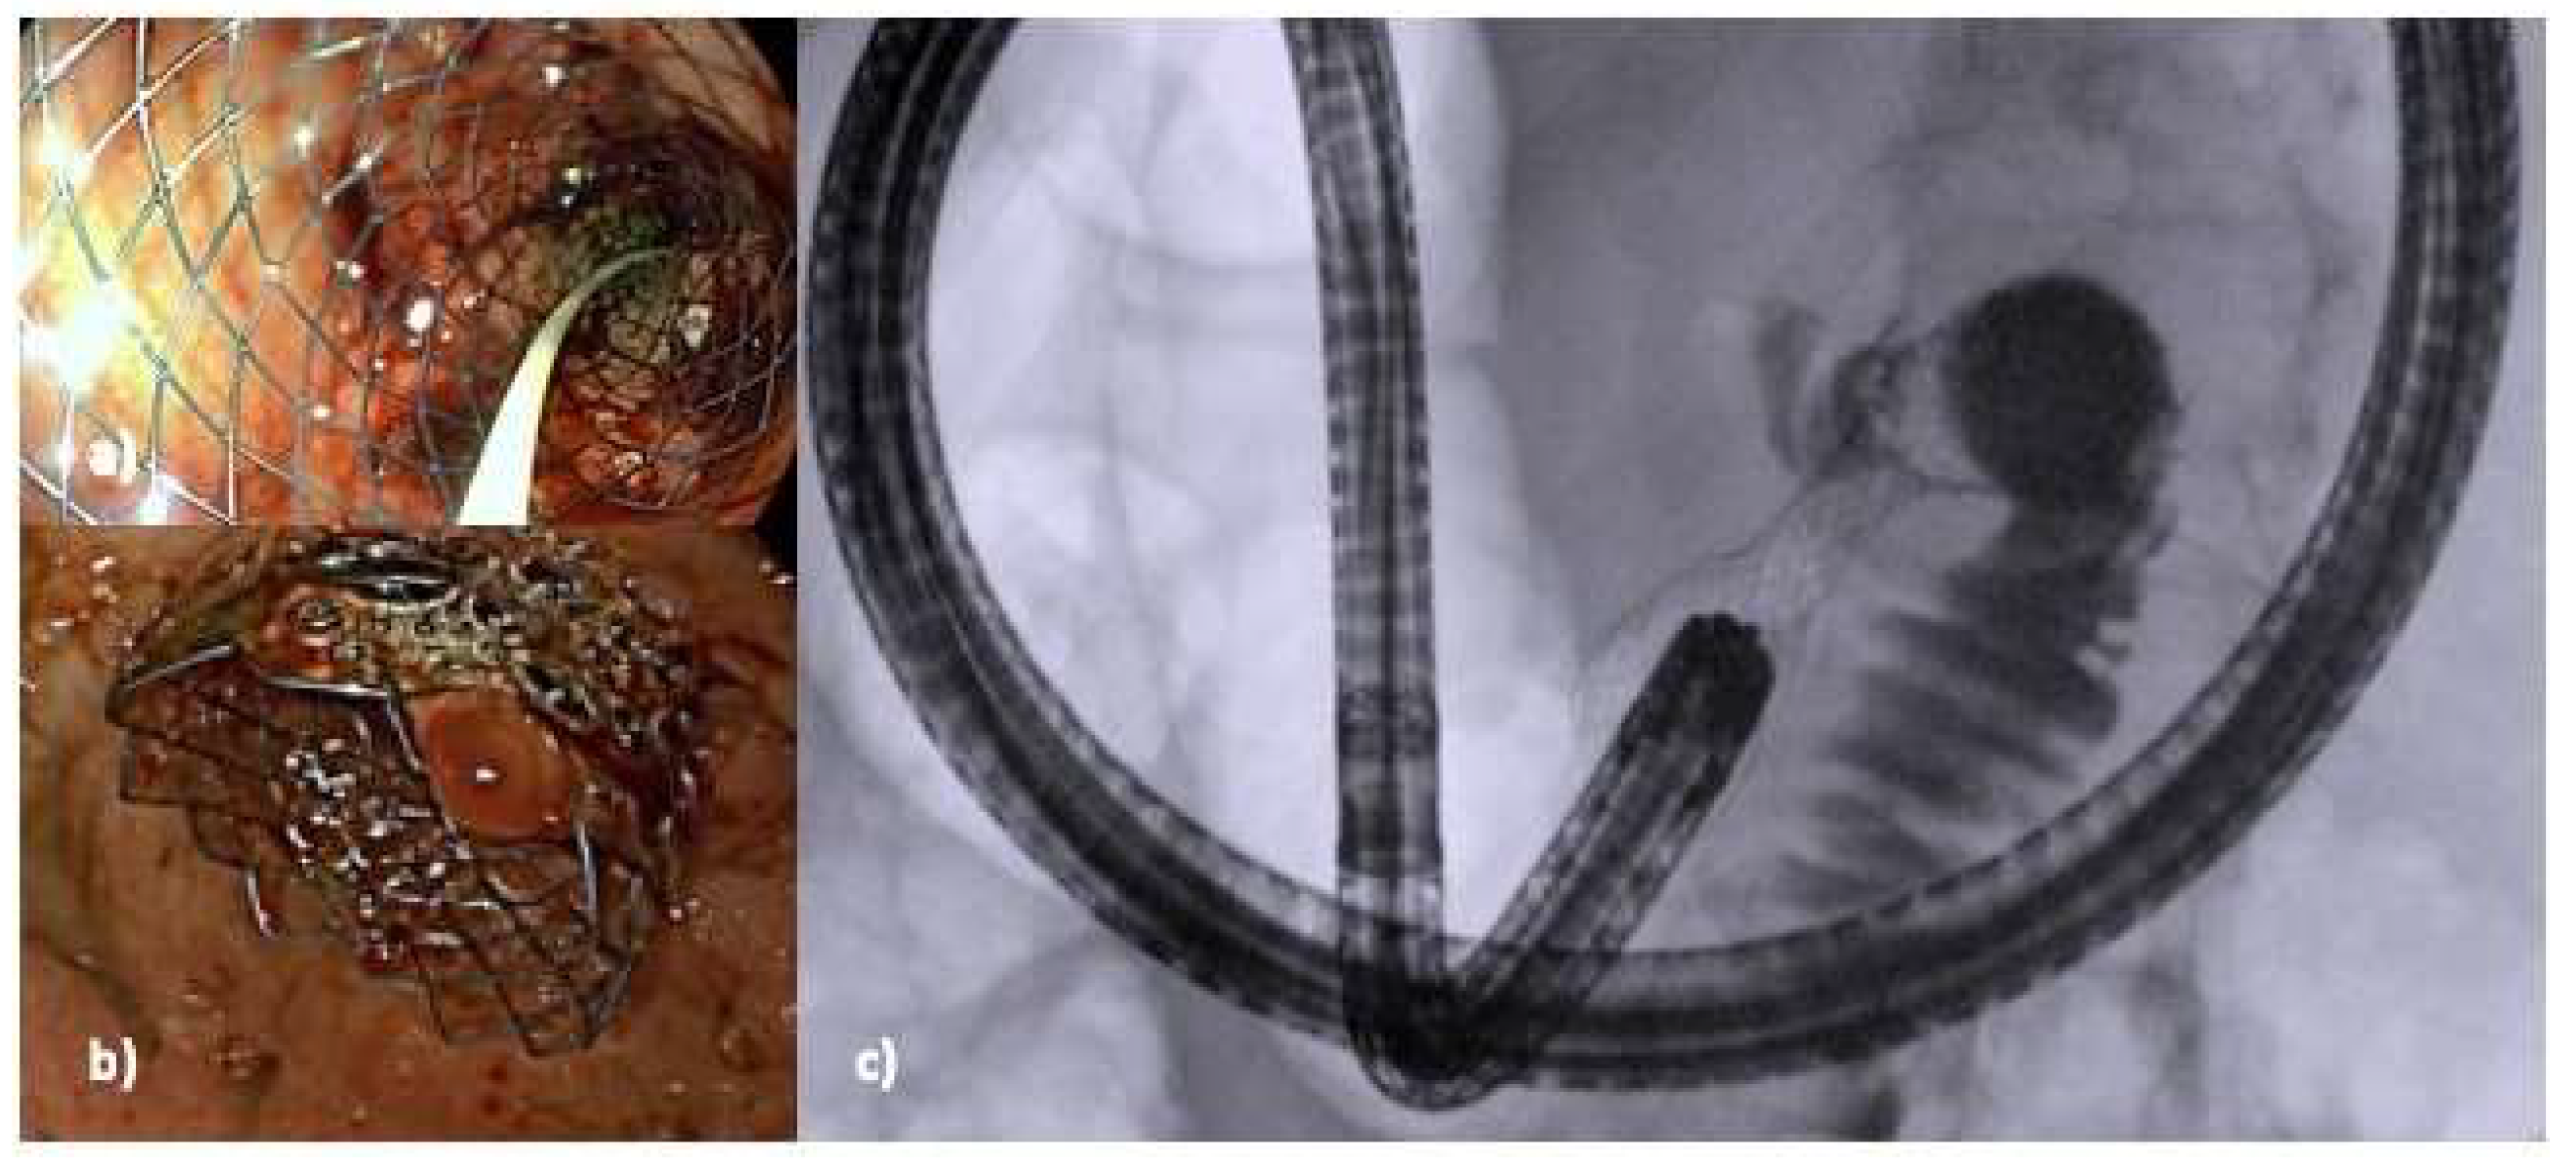

5.2. Device-Assisted EUS-GE

5.2.1. Ultraslim Endoscope-Assisted Technique

5.2.2. Endoscopic Ultrasound Double Balloon-Assisted Technique

5.2.3. Nasobiliary Drain-Assisted Technique

5.2.4. Endoscopic Ultrasound-Guided Double Balloon-Occluded Gastrojejunostomy Bypass